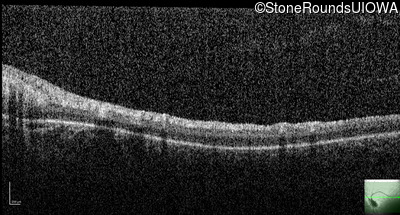

Optical Coherence Tomography - Right - No Light Perception

Exemplar / OCT Stack